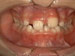

Missing lateral incisors